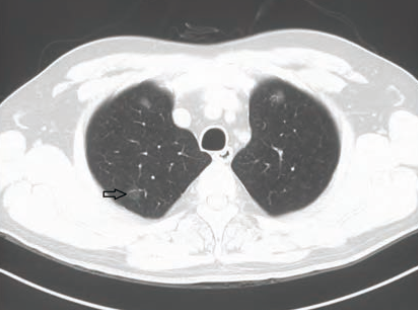

磨玻璃结节是影像学上的一种描述,一般指的是肺内可见密度增高类圆形局限的阴影,所谓叫磨玻璃结节指的是密度像一层磨砂玻璃样的一种密度,因此叫做磨玻璃结节,一般小于3cm的称为结节,大于3cm的成为肿块。

磨玻璃结节是肺部通过薄层CT影像学描述的一类结节影专用名词,是指肺内有局灶性结节样密度增高,磨玻璃结节可能是炎症,临床上常见的炎症为支原体感染、真菌感染、结核分枝杆菌感染所致,建议患者及时就诊,明确炎症类型。